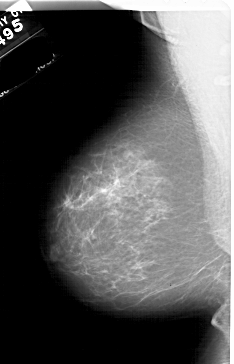

A_1767_1.RIGHT_CC

RIGHT_CC LINES 6091 PIXELS_PER_LINE 3691 BITS_PER_PIXEL 12 RESOLUTION 43.5 OVERLAY